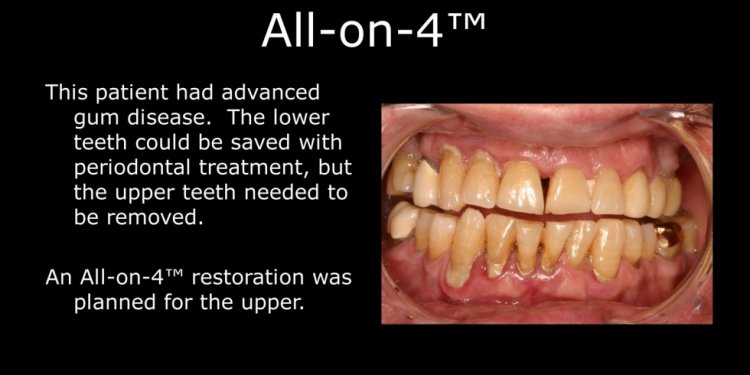

Dental Implants and Gum Disease

What is gum disease? Periodontal disease (gum disease) is a chronic bacterial infection of the gums and bone supporting the teeth. It is a major cause of tooth loss in adults. However, because gum disease is usually painless, you may not even know you have it. Gum disease is caused by plaque bacteria which form a sticky film on the tooth surface. These plaque bacteria release…